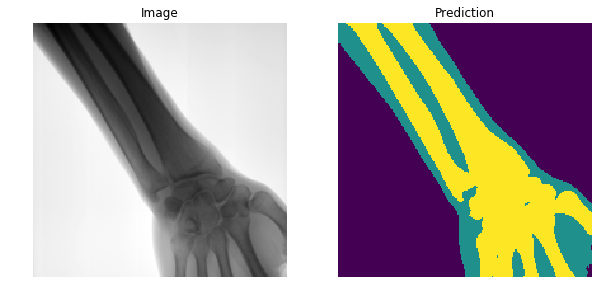

XNet

-

Original Architecture based on SegNet but fewer parameters.

- Trained on 150 images, artificially augmented to more than 7000.

Results

- Generalises well even for unseen categories!

- Overall accuracy on test set: 92%

- Soft tissue TP/FP rate: 82% / 4%